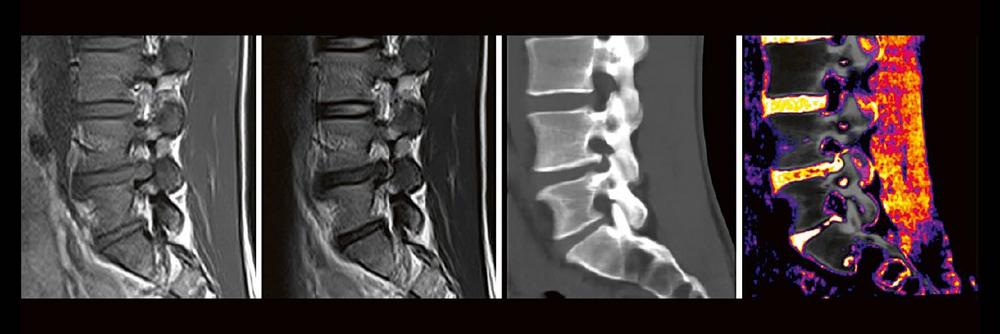

Die Dual-Energy-Computertomographie (DECT) hat für viele klinische Anwendungen bereits Einzug in die Praxis genommen. Für die Behandlung von Wirbelsäulenerkrankungen sind besonders die Darstellung von Knochenmarkveränderungen (z. B. bei osteoporotischen Frakturen) und der Bandscheibe (z. B. bei Bandscheibenvorfällen) interessant und werden intensiv beforscht. Hierdurch versprechen wir uns eine schnellere Therapie für unsere Patienten, weil viele Befund bereits in der CT erhoben werden können, die zuvor nur mit MRT sinnvoll abgebildet werden konnten. Darüber hinaus erhoffen wir uns wertvolle Zusatzinformationen bei degenerativen, traumatischen und entzündlichen Erkrankungen des Achsenskeletts.

In zwei kurzen Übersichtsvorträgen werden die Referenten einen Überblick über die Technik und klinische Anwendung der DECT bei den oben genannten Wirbelsäulenerkrankungen geben. In einem praktischen Teil können Sie anschließend die Technik mit Hilfe des BerlinCaseViewers anhand klinischer Fallbeispiele testen. Mit Hilfe der Fälle besprechen wir Nutzen aber auch Grenzen der Technik und zeigen mögliche Perspektiven für zukünftige Anwendungen auf.